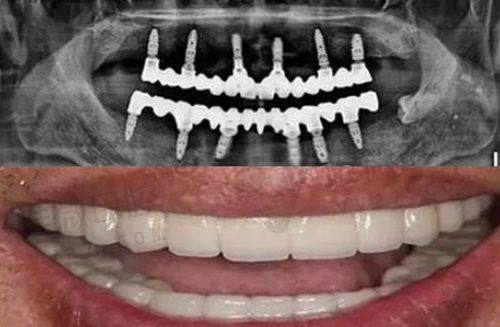

在了解价格之前,咱先说说啥是种植牙。简单来说,种植牙就像是给咱们的牙齿重新“种”上一个根。它可不是真的种上一颗牙,而是把人工牙根植入到牙槽骨里,等牙根和牙槽骨长在一起后,再安装牙冠。这样种出来的牙和咱们自己的真牙差不多,能正常吃饭、说话,外观上也看不出来区别。

下面就给大家详细看看成都贝臣口腔医院的种植牙价格表。这里面包含了不同品牌和种植方式的价格,大家可以根据自己的需求和经济情况来选择。